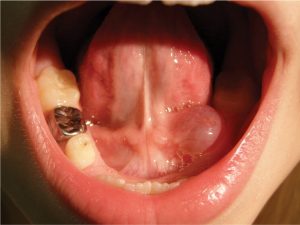

Mucocèle

Une mucocèle n’est pas une croissance kystique nuisible. Elle se produit lorsque la salive fuit d’une glande salivaire endommagée et s’accumule pour former une petite bosse blanche en forme de sac. Les kystes de mucocèle sont parfois douloureux.